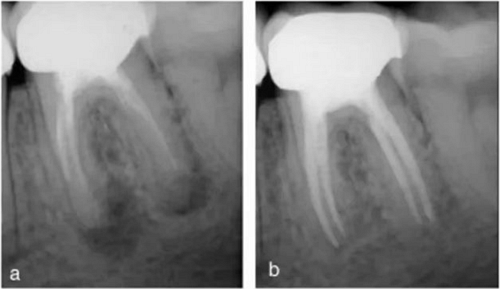

異于雙根的下頜第一磨牙的解剖形態(tài)變異主要為存在一個(gè)額外的位于遠(yuǎn)舌側(cè)【radix entomolaris(RE)】或近頰側(cè)【radix paramolaris(RP)】的牙根(圖 13)。在白種人和非洲人中發(fā)生這種牙根異常形態(tài)的概率不超過 5%,然而在黃種人中(比如中國(guó)人、因紐特人、印第安人)遠(yuǎn)舌根發(fā)生率在 5%至超過 30%之間。位于頰側(cè)的近頰根罕見,發(fā)生率低于 0.5%(。遠(yuǎn)舌根的外形大小可從小圓錐形變化至正常長(zhǎng)度和根管的“成熟的”牙根。

一般來說,遠(yuǎn)舌根比遠(yuǎn)頰根和近中根小,可能獨(dú)立于或部分融合于其他牙根。臨床治療過程中,當(dāng)懷疑存在額外的牙根時(shí),需要根據(jù)準(zhǔn)確的放射學(xué)診斷、臨床檢查、開髓洞型預(yù)備進(jìn)行判斷。在術(shù)前的放射片中,若遠(yuǎn)中根輪廓或根管的視野或外形不清楚,可能表明存在“隱藏的”牙根。在近中或遠(yuǎn)中成 30 度角的方向上拍攝第二張放射片,通??梢燥@示遠(yuǎn)舌根的輪廓。

使用牙周探針對(duì)牙冠或牙頸部形態(tài)進(jìn)行臨床檢查有助于發(fā)現(xiàn)額外的牙根。一個(gè)額外的牙尖(副磨牙結(jié)節(jié),tuberculum paramolare)或明顯突出的遠(yuǎn)頰或遠(yuǎn)舌小葉,伴有頸部的突出,可能表明存在額外的牙根。遠(yuǎn)舌根的根管口位于主要的遠(yuǎn)中根管的近舌側(cè),因此開髓洞型需要預(yù)備成矩形或梯形。使用牙髓探針仔細(xì)檢查髓室底的暗色的發(fā)育溝,可以精確的定位遠(yuǎn)舌根根管口。

使用手術(shù)顯微鏡是非常有幫助的,特別是在那些根管口被鈣化物覆蓋的病例中,這些鈣化物可以使用超聲尖或長(zhǎng)柄小球鉆輕松去除(圖 14a-d)。